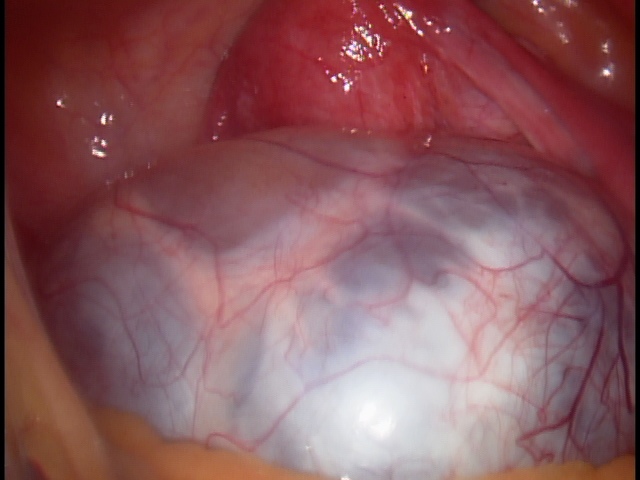

Ooforoplastia é a técnica em que se remove o cisto do ovário, preservando o restante do mesmo. Indicado para mulheres em idade fértil, que desejam a preservação da fertilidade.

Ooforectomia é a remoção do ovário. Indicada nos cistos de ovários em pacientes que já estão na menopausa, nos casos de câncer de ovário, entre outros.